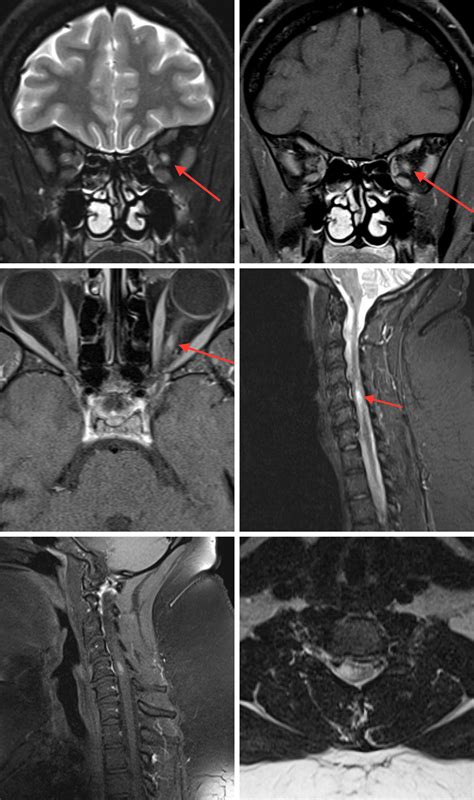

To understand a T2 hyperintense lesion, one must first understand how an MRI functions. MRI technology uses magnetic fields to detect water molecules in the body. Different sequences are used to highlight different tissues; T2-weighted imaging is a specific setting where water and fluid-rich tissues appear bright (hyperintense) against the darker background of healthy brain tissue.

When a radiologist identifies a "lesion," they are describing an area that looks different from the surrounding tissue. Because T2 imaging is highly sensitive to water, these areas often show up as bright white spots. These spots can be caused by a wide range of factors, including:

• Normal aging processes (often referred to as white matter hyperintensities).

• Previous minor injuries or scarring in the brain.

• Inflammatory responses or localized swelling.

• Demyelinating conditions or vascular changes.